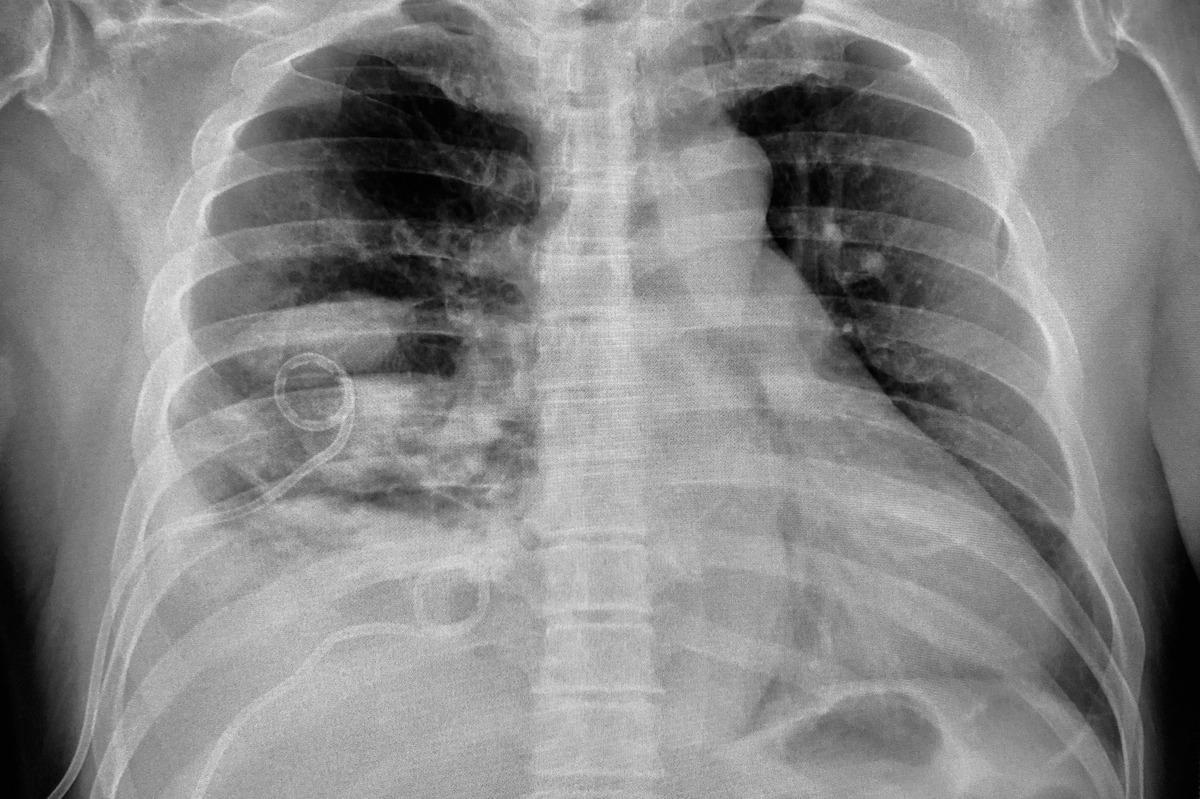

The progression of empyema can be characterized by a series of events. The exudate stage is characterized by an increase in fluid production in the pleural cavity during an inflammatory process such as pneumonia. Microorganisms, most often bacteria, start colonizing the fluid and cause empyema as the disease progresses. This fluid contains higher levels of neutrophils, proteins, lactate dehydrogenase, and dead cells. The fibrinopurulent stage is characterized by a thick opaque fluid. Following the resolution of the infection, as a result of the inflammation, a fibrotic process occurs that can lead to the limitation of the lung parenchyma.

Image Credit: Good Image Studio/Shutterstock